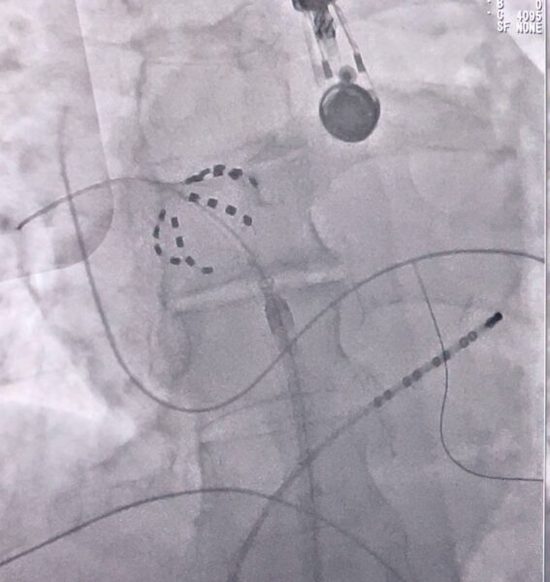

5 листопада 2024 року в ДУ «Національний інститут серцево-судинної хірургії ім. М.М. Амосова НАМН України» вперше в Україні проведено серію абляцій ізоляції легеневих вен із використанням інноваційної не-термальної технології — електропорації (PFA).

Це метод нового покоління, який швидко та безпечно дозволяє ізолювати аритмогенні ділянки, уникаючи ризиків, пов’язаних із температурними методами (кріо- та РЧ-абляція).

– Вибірково впливає лише на кардіоміоцити — без ушкодження стравоходу, діафрагмального нерва чи судин.